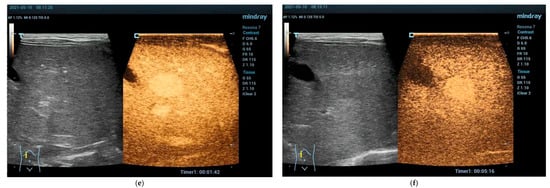

Focal Nodular Hyperplasia (FNH)

- Fang, C.; Bernardo, S.; Sellars, M.E.; Deganello, A.; Sidhu, P.S. Contrast-enhanced ultrasound in the diagnosis of pediatric focal nodular hyperplasia and hepatic adenoma: Interobserver reliability. Pediatr. Radiol. 2019, 49, 82–90. [Google Scholar] [CrossRef]